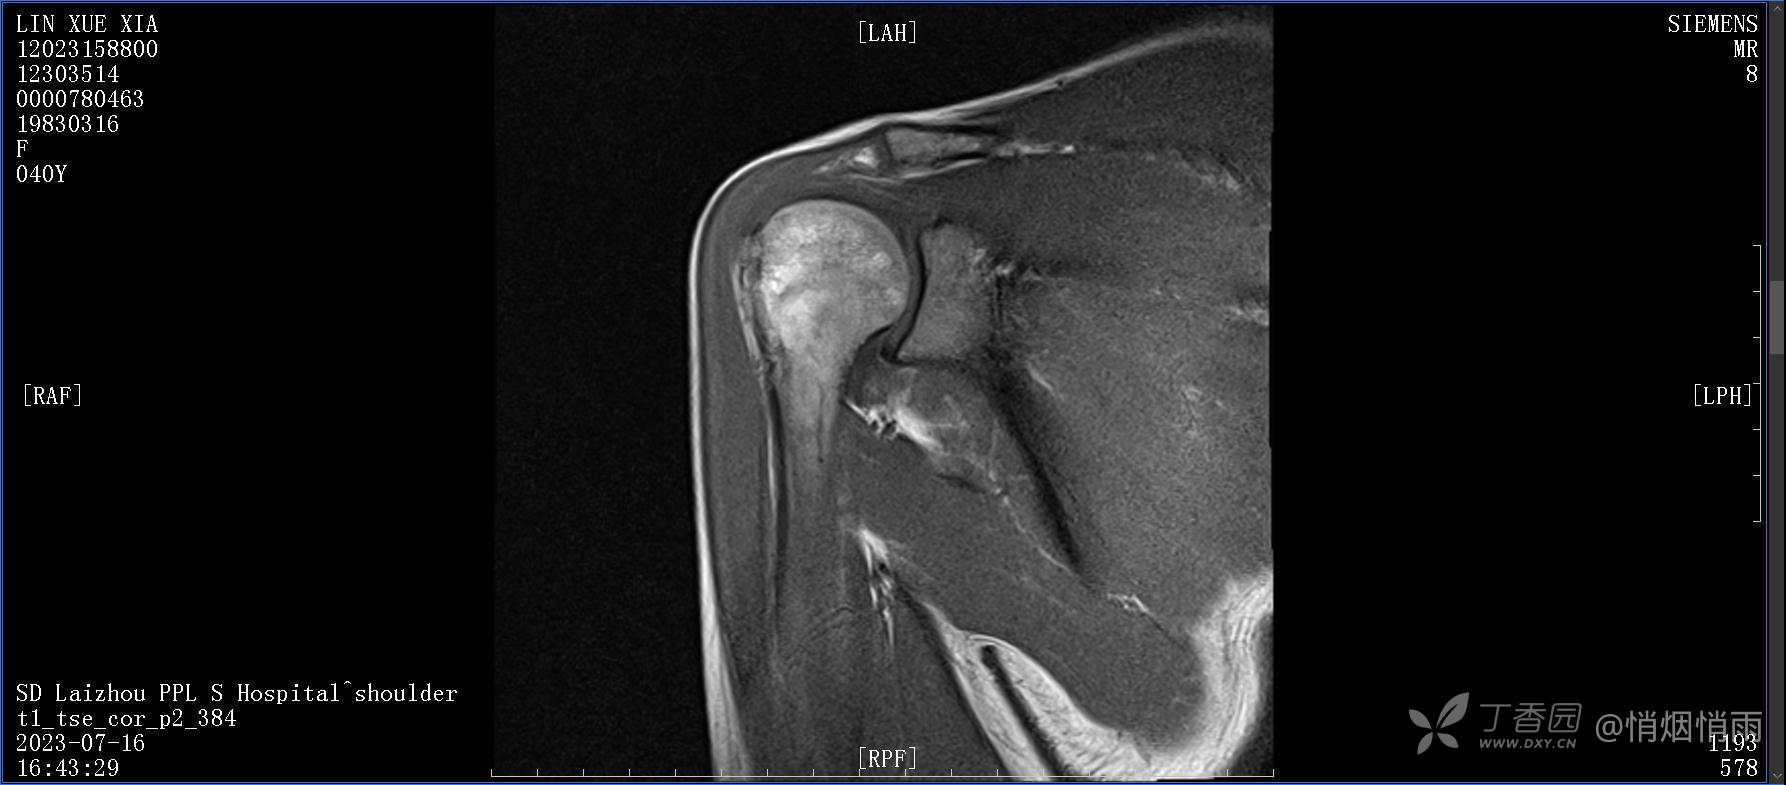

查体:右肩关节局部轻度肿胀,肩胛区压痛明显,痛处不固定,肩关节痛性活动受限,jobe test(+),lift -off test(+),中指、环指感觉较余指减退,余肢端感觉及血运情况可。

目前的诊断,暂时依据辅助检查诊为肩袖损伤,但是患者疼痛的性质和特点,却不是单纯的肩袖损伤所致。考虑过胸廓出口综合征,但是该疾病会出现肩胛区的疼痛吗?(由于考虑到费用的问题,没再进行下一步的检查)带状疱疹会有如此的症状吗?